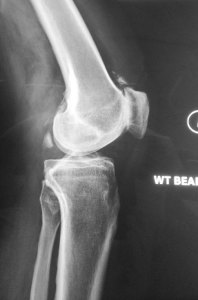

X-rays showed mild narrowing of the medial compartment of his left knee. In addition, there was an obvious severe osteoarthritis of the patellofemoral joint (kneecap joint).

An MRI scan of his left knee showed a root tear of the posterior horn of his medial meniscus with loss of hoop stress, extrusion of the medial meniscus together with subchondral oedema of the medial tibial-femoral compartment and thinning of the cartilage of the medial compartment of his left knee.

In addition, the osteoarthritis of the kneecap compartment was also seen.

The MRI also confirmed that the lateral knee compartment was healthy and that the central cruciate ligaments were intact.